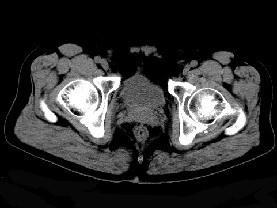

问题 男,56岁,因左髋关节疼痛、无外伤史,体检左髋关节稍肿胀,请结合所提供图像,选择最佳选项 ( )

选项 A、左髋关节滑膜炎 B、左髋关节类风湿关节炎 C、左髋关节退行性改变 D、左髋关节痛风 E、左髋关节滑膜骨软骨瘤病

答案 E